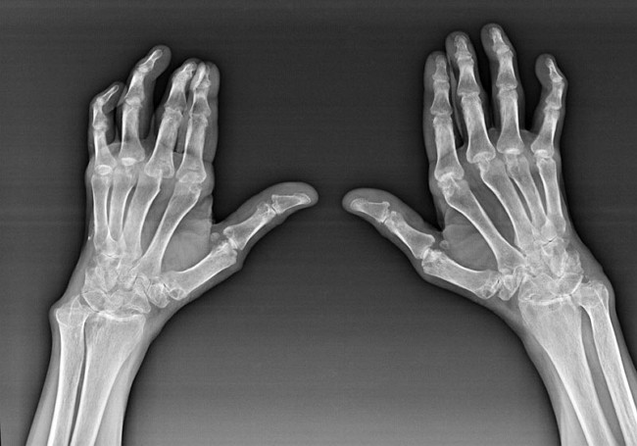

Apesar do fato de a artrite reumatóide ser uma doença sistêmica sob ela, em maior medida, as articulações sofrem, enquanto a lesão de outros tecidos e órgãos está em segundo plano. Com esta doença, quase todos os tipos de articulações de escova podem ser afetados (Wristwalls, pathas de carpo, metacarpal-phalanx, juntas inter-phalanx). A lesão é geralmente simétrica (aqueles. As mesmas articulações são afetadas) em ambas as mãos, acompanhadas de inchaço, dor nas articulações danificadas. De manhã, durante o levantamento da cama, há alguma rigidez nas articulações afetadas, que podem durar cerca de 1 hora e depois desaparecer sem deixar rasto.

Muitas vezes com artrite reumática perto das juntas afetadas do pincel (Mais frequentemente, as articulações piano-phalanx, inter-falanx) Nódulos reumatóides aparecem. Eles são uma formação arredondada localizada sob a pele. No pincel, essas formações surgem com mais frequência nas costas. Na palpação, eles são densos, inativos, indolores. O número deles pode variar.

Diagnóstico das causas da dor

As mãos da dor nas articulações da mão estão envolvidas no diagnóstico e tratamento das causas da dor, principalmente um traumatologista e médico da criação de A. Para diagnosticar essas razões, esses médicos usam principalmente clínicos (Coleção de anamnese, inspeção externa, palpação, etc.), radial (Radiografia, tomografia computadorizada) e laboratório (Exame de sangue geral, exame de sangue bioquímico, etc.) Métodos de pesquisa.

Quando lesões do pincel, você deve consultar um traumatologista. Os principais métodos de diagnóstico que são usados na prática médica para identificar danos traumáticos ao pincel (fraturas, deslocamentos, ligamentos, hematomas), são um exame externo, anamnese, métodos de radiação de pesquisa (Radiografia, tomografia computadorizada).

A coleta de dados anamnestic permite que o médico identifique incidentes que levaram ou podem levar a uma lesão no pincel. A história da anamnese também é usada para esclarecer os sintomas que incomodam o paciente. Durante um exame externo no pincel, é possível detectar inchaço, hematomas, sua deformação, limitação da mobilidade articular. Com a ajuda da palpação, o médico revela a presença de dor, violação da forma anatômica da articulação, danos aos ligamentos. Métodos de radiação de pesquisa (Radiografia, tomografia computadorizada) Eles permitem que você confirme o diagnóstico, pois durante seu uso, os danos mecânicos às formações anatômicos do pincel são claramente visíveis.